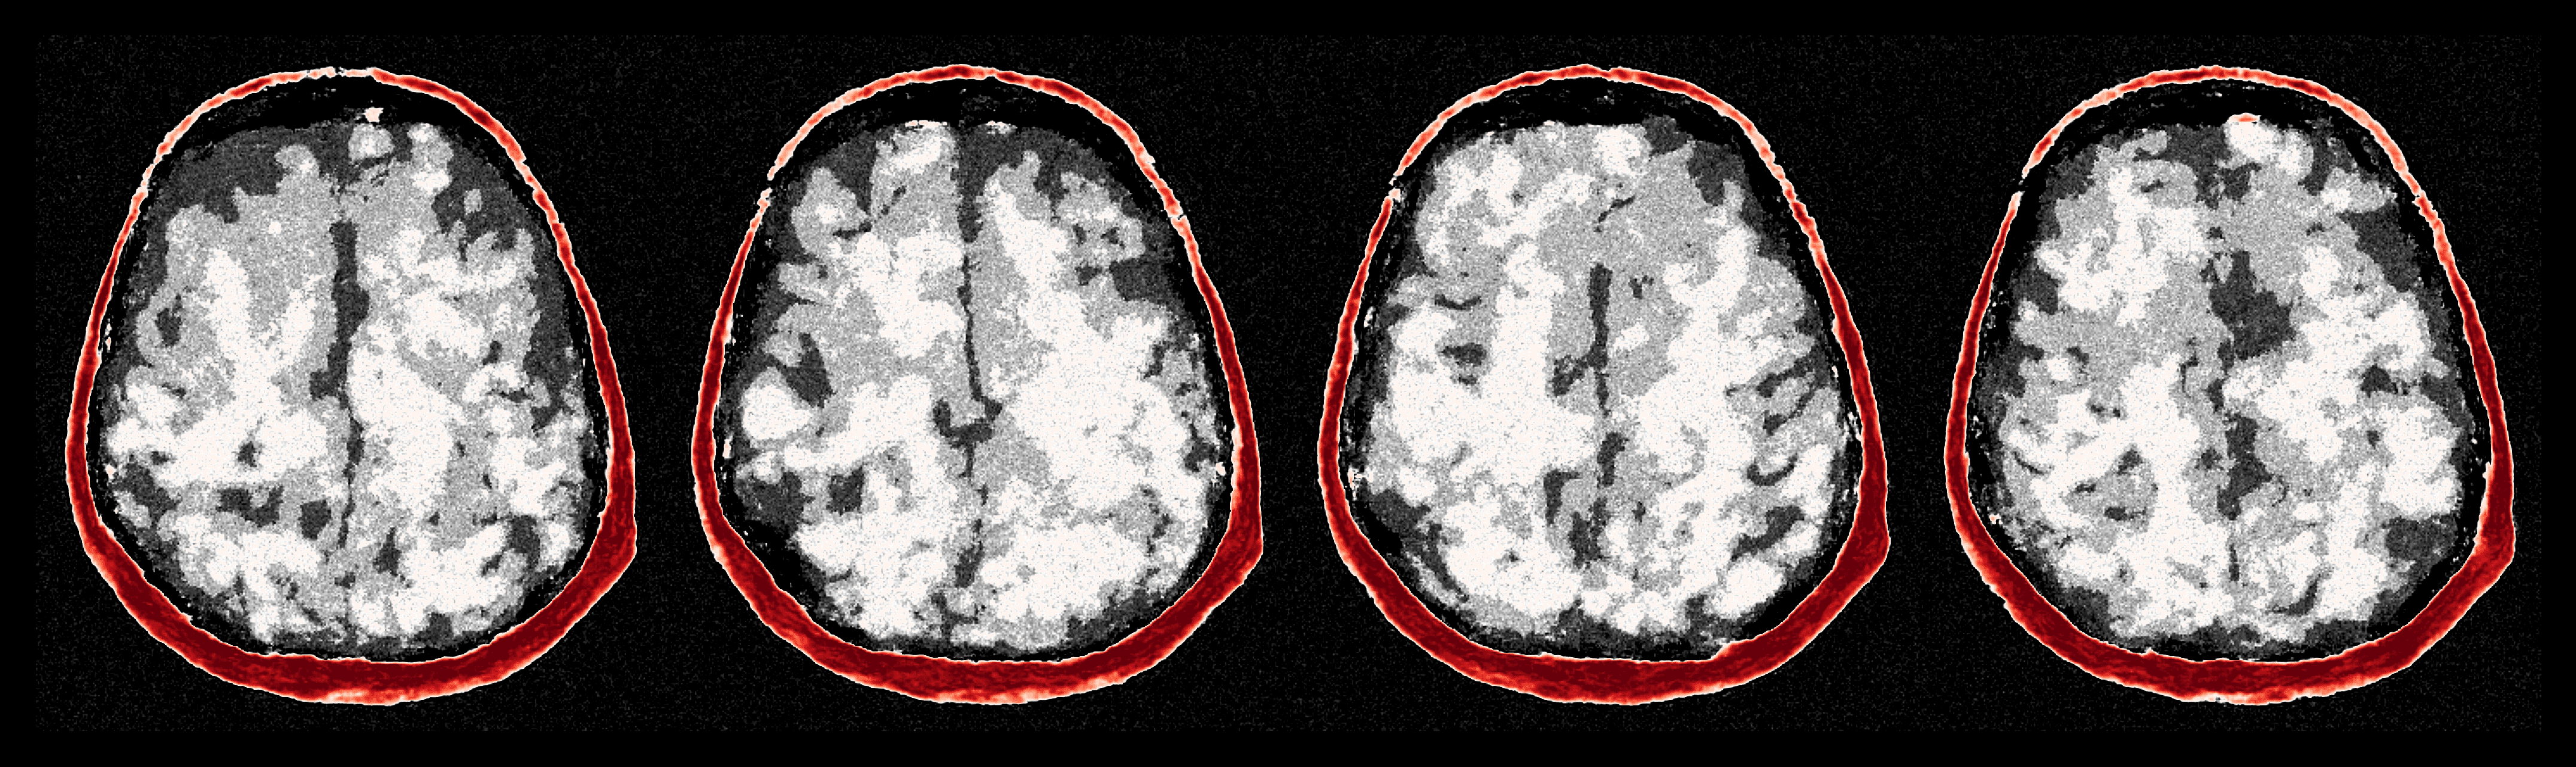

To visualize uncertainty, we calculate uncertainty images by taking the pixel-wise standard deviations as defined in Equation 10 with posterior samples. Figure 12 shows uncertainty images for four iterations of ASPIRE alongside the error of the posterior mean from the ground truth. From these figures, we make the following qualitative observations: (1) uncertainty images increase in resolution with each ASPIRE refinement (2) refinements increase correlations between the uncertainty and the error. Specifically, the errors concentrate near the top and lower-right of the internal brain tissue. The reason being that high acoustic contrast in these areas is creating multiple reverberations of the wavefield inside the brain impeding accurate imaging, importantly these are areas that are highlighted by the uncertainty. Correlations between the uncertainty and the error constitute important empirical evidence of the trustworthiness of the uncertainty. To more rigorously quantify this correlation, and quantitatively validate the uncertainty quantification, we study the calibration of our uncertainty in the following section.

5.1 Amortized uncertainty quantification